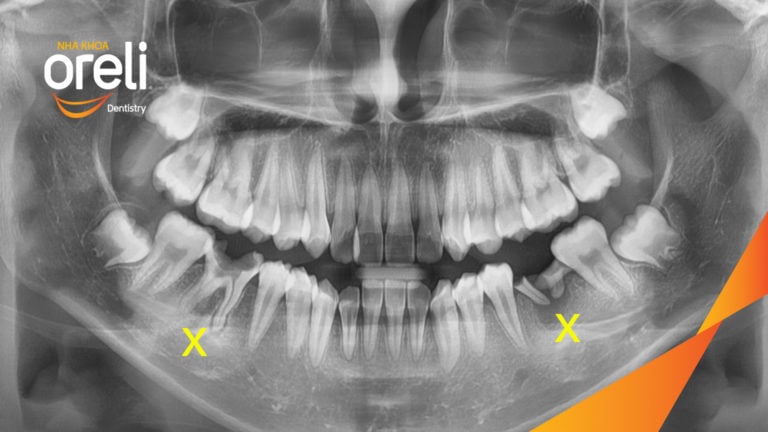

Ca niềng chỉnh hô nhổ 2 răng 4 hàm trên di gần răng 7 8 hàm dưới cho nụ cười đẹp – Kết quả sau hơn 2 năm ở Oreli Niềng răngDi gần răng 7 8Hô Xem thêm